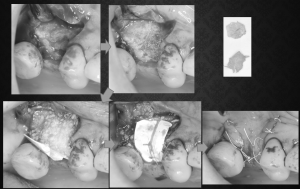

今日はインプラントが後に入ることが前提(インプラントを入れたいが骨幅が足りない状況でした)の造骨処置を行いました。患者さんは他院でマイクロスコープ下での根管治療を自費でやっていたのだそうですが、一向に治らない、治療が進まない、説明もなく歯を抜かれた、インプラントは骨がないからできない等々、様々な不満を抱えて2年ほど前に来院されました。咬合や根管治療の予後不良、上顎両側臼歯部欠損など、多くの問題を抱えていましたが、シンラシステムによる咬合分析とそれに基づいた診査診断、建築士が図面に設計図を描くように、模型上に蝋で治療設計を具現化していきました。要再根管治療歯が2本あり、1本は治癒しましたが、もう1本は残念ながら予後不良で抜歯となりました。もともと存在していた根尖病変が比較的大きかったため、抜歯後の骨回復は十分でないと予想していました。既にほかの部分である天然歯の補綴、上顎臼歯部にインプラント治療をするうえで骨不足確認後、サイナスリフト(副鼻腔内造骨処置)を行い、その後のインプラント治療は終了しており、残る部分はここのみとなっていました。前歯は手を付けないでほしいとのことだったので完全とは言えませんが、ほぼフルマウスリコンストラクションのケースでした。

福岡で先月、水上哲也先生に教わった技術を早速活かすことができました。もともと歯周組織再生療法の手技上における考え方の変化を講義と実習で学ぶ形式でした。しかし、その手技は他の外科にも応用できることも動画で解説がありました。考え方と道具が変わったことで、より楽に、綺麗に、短時間での手術が可能になったのではないかと感じます。ストレスがだいぶ減ったと感じます。具体的には、以前は歯肉を骨から剥離するのに時間がかかったり(肉芽が複雑な骨欠損形態に入り込んでいる場合がある時など)、骨補填材やそれを覆う人工膜が露出しないように減張切開と言われれる切開を大きく入れる必要があったり(術後の腫れの原因となる)、歯肉がだぶつくような縫合形態が推奨されていた時代があり(きれいなオペに見えない)ましたが、今回学んだことで、その辺の部分がだいぶ解消されたのではないかと思いました。以前によく使用していたゴアテックス社の縫合糸ですが、同社が歯科業界から撤退の動きがあり、その縫合糸に代わるものが望まれていましたが、同セミナーの中で、国内のメーカーで、より使用感のいい糸が紹介されたので早速使い始めました。また基本となる切開に対する気の使い方、歯肉がきれいに寄り添う縫合の仕方など模型実習を通して理解を深めることができましたのが今回の実践に活きたのではないかと思います。お金と時間を使って学び、昨日までの自分よりも進化できる環境にいることに感謝し、日々精進したいと思います。